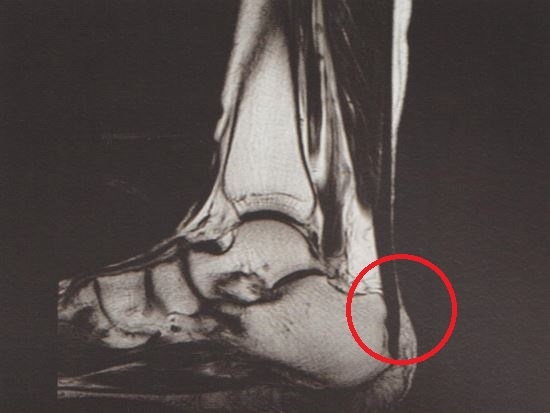

아킬레스건 부착부 주변, 특히 종골 융기 부위와 건 주변의 압통점을 중심으로 치료를 진행합니다.

발목 부위는 아킬레스건뿐 아니라 다양한 근육, 인대, 신경 구조가 복잡하게 얽혀 있는 부위입니다. 따라서 보다 정확한 치료를 위해서는 내부 구조를 확인하는 과정이 중요합니다.